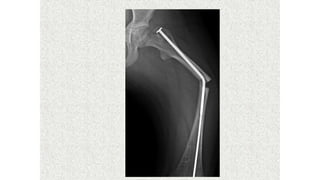

This document discusses a disease and its investigation and management. It begins by introducing Dr. Aniket Wankhede from MGIMS Sevagram and asks what the disease is. It then asks how the disease happens and discusses its causes. Next it asks how the disease appears on x-rays and describes symptoms some people experience living with it. Finally, it asks how the disease will be investigated and managed.